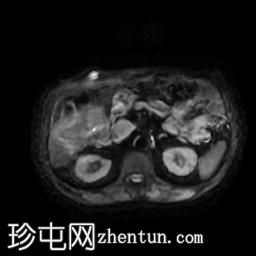

MRI

轴位T2加权像

脂肪抑制像

轴位

T2加权像

胆囊切除术后,可见肝总管局部断裂,尤其是在胆囊管开口上方。该断裂伴有胆囊切除部位形成较大的血肿或胆汁瘤。

胆管损伤可能发生在手术过程中,导致胆汁渗漏到周围组织,从而形成血肿或胆汁瘤。这可能出现明显的临床症状,并可能需要进一步干预,具体取决于病情的严重程度和患者的临床表现。